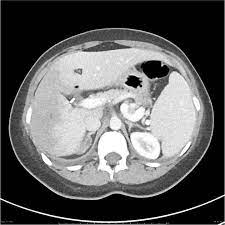

Chiasmata -mə-tə or chiasmas also chiasms 1. Esophageal varices are extremely dilated sub-mucosal veins in the lower third of the esophagus. Located in metro Denver northern Colorado and western Nebraska serving all of the Front Range our team consists of board-certified and fellowship-trained interventional radiologists. This results in hepatic congestion similar to Budd-Chiari syndrome and post-sinusoidal portal hypertension. The patients condition should be monitored throughout the procedure. They are most often a consequence of portal hypertension commonly due to cirrhosis. Toxic injury to liver sinusoids causes sloughing of endothelial cells that embolize to hepatic venules and cause eventual fibrosis of the venules. Coin in the Esophagus. There is no clear consensus regarding the number of occluded veins some authors claim that there should be at least one occluded hepatic vein 7 others state that there are no significant.

Carcinoma of the Colon. Budd-Chiari syndrome a blockage in one or more veins that carry blood from the liver back to the heart. And coumarin skin necrosis adrenal gland hemorrhage and infarction. Toxic injury to liver sinusoids causes sloughing of endothelial cells that embolize to hepatic venules and cause eventual fibrosis of the venules. Chiari malformation CM is a structural defect in the cerebellum characterized by a downward displacement of one or both cerebellar tonsils through the foramen magnum the opening at the base of the skull. Embolism and thrombosis of. La présence dune ou plusieurs affections prothrombotiques est fréquente La prise en charge repose sur un traitement anticoagulant précoce le traitement de l.